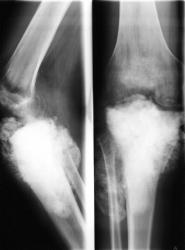

Случай № 3. "Распространение" остеосаркомы через зону росткового хряща на эпифиз и суставную поверхность у 16 - ти летнего пациента.

Остеосаркома "не переходит" через зону росткового хряща на эпифиз - дифференциально-диагностический признак.